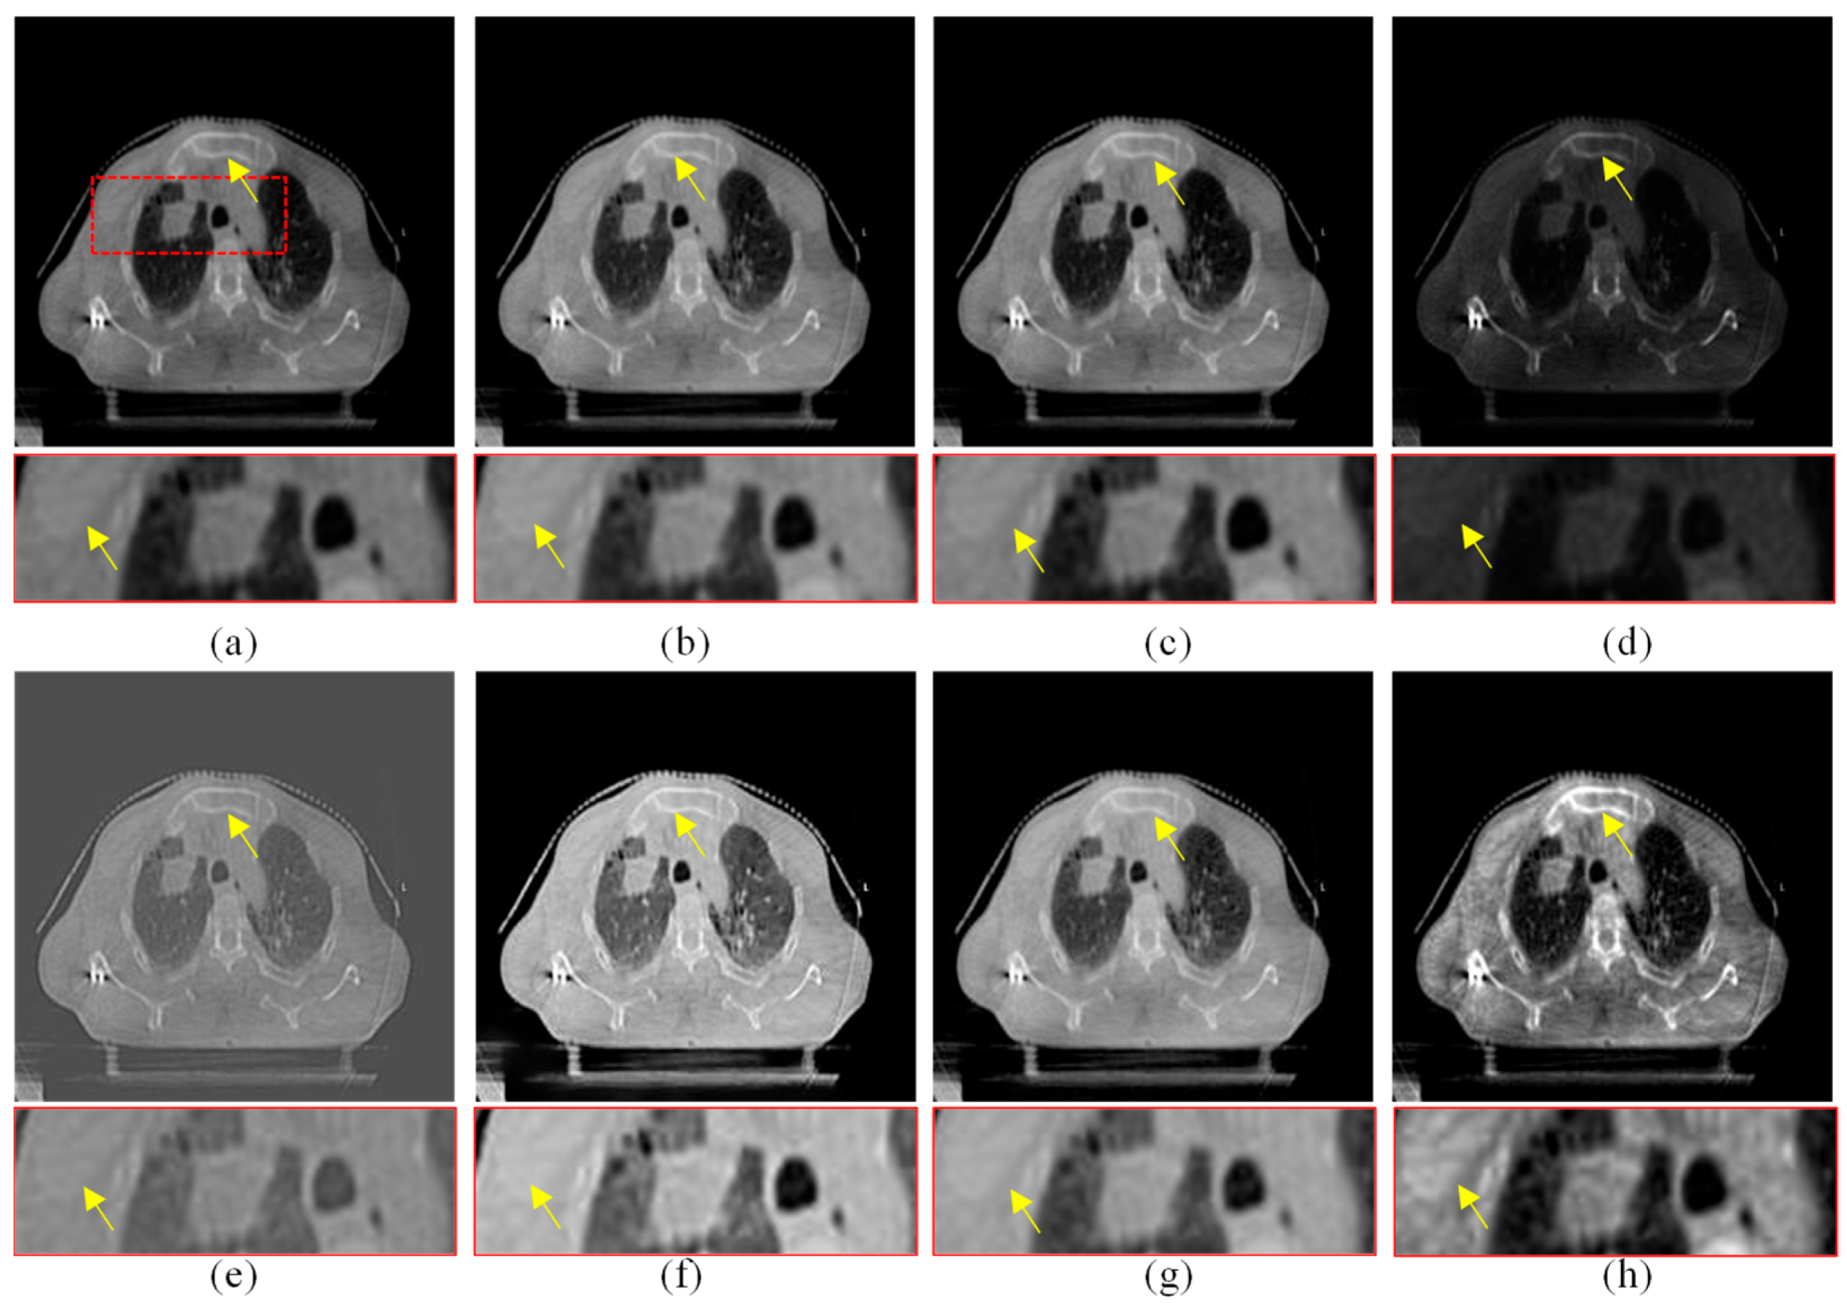

Figure 8.

Enhanced results of pair 2. (a) Source CBCT images. (b) MSR. (c) MSRCR. (d) DCP. (e) CBF. (f) RRM. (g) SMIPC. (h) Ours.

Figure 9.

Enhanced results of pair 3. (a) Source CBCT images. (b) MSR. (c) MSRCR. (d) DCP. (e) CBF. (f) RRM. (g) SMIPC. (h) Ours.

Figure 10.

Enhanced results of pair 4. (a) Source CBCT images. (b) MSR. (c) MSRCR. (d) DCP. (e) CBF. (f) RRM. (g) SMIPC. (h) Ours.

Another three sets of experiments are shown in Figure 8, Figure 9 and Figure 10. As can be seen from the enlarged regions and the yellow arrows in Figure 8, it is difficult to directly observe the presence of skeletal information at this position from the enlarged region in Figure 8a. The enhancement results of the comparison methods also did not improve the visual contrast in this region, but the skeletal information can be clearly observed in our result, which means our results outperform the comparison algorithms in terms of detail, contrast, and visualization effect.

The same conclusion can also be obtained in Figure 9 and Figure 10. Especially in the enalrged region in Figure 10, our results provide a much clearer organizational structural and edge infromation, which is very helpful for disease diagnosis and treatment. Through comparison, it can be found that the rigidity informaiton in our results is more significant, the tissue edge in our results is clearer, and the contrast of the texture structure is also better than that of the comparison algorithms. The observation effect is greatly improved by our enhancement method, proving that our method can effectively enhance the CBCT images.